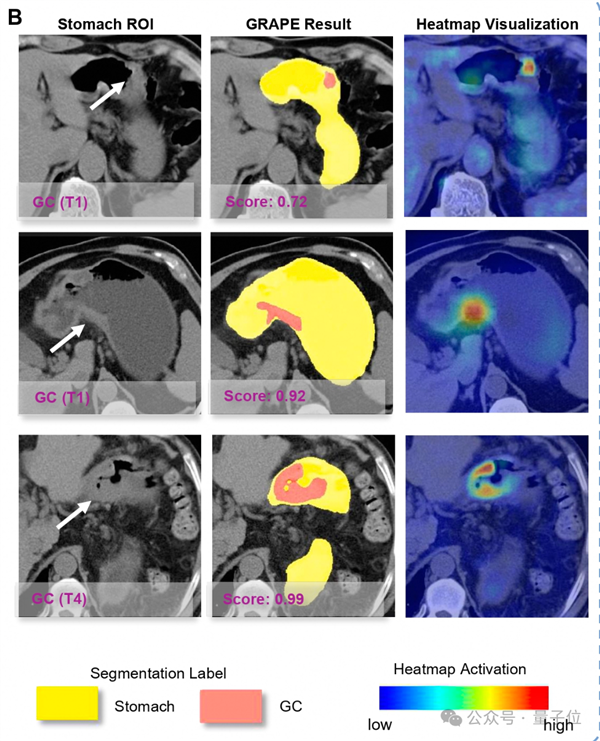

DAMO GRAPE的敏感性和特异性分别达到85.1%和96.8%,相比起人类放射科医生分别提升21.8%和14.0%。

△AI成功从平扫CT识别早期胃癌